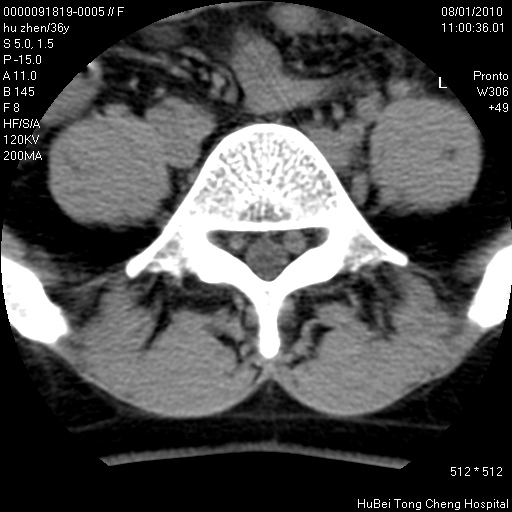

患者 女,36岁。右侧腰腿痛半月余。腰骶椎mr平扫偶然发现骶椎异常信号。

临床诊断:1)腰椎间盘突出症。2)骶椎肿瘤性病变?

骶椎ct平扫(层厚、层距均为5mm),图像如下:

考虑s1骨纤维异常增殖症。